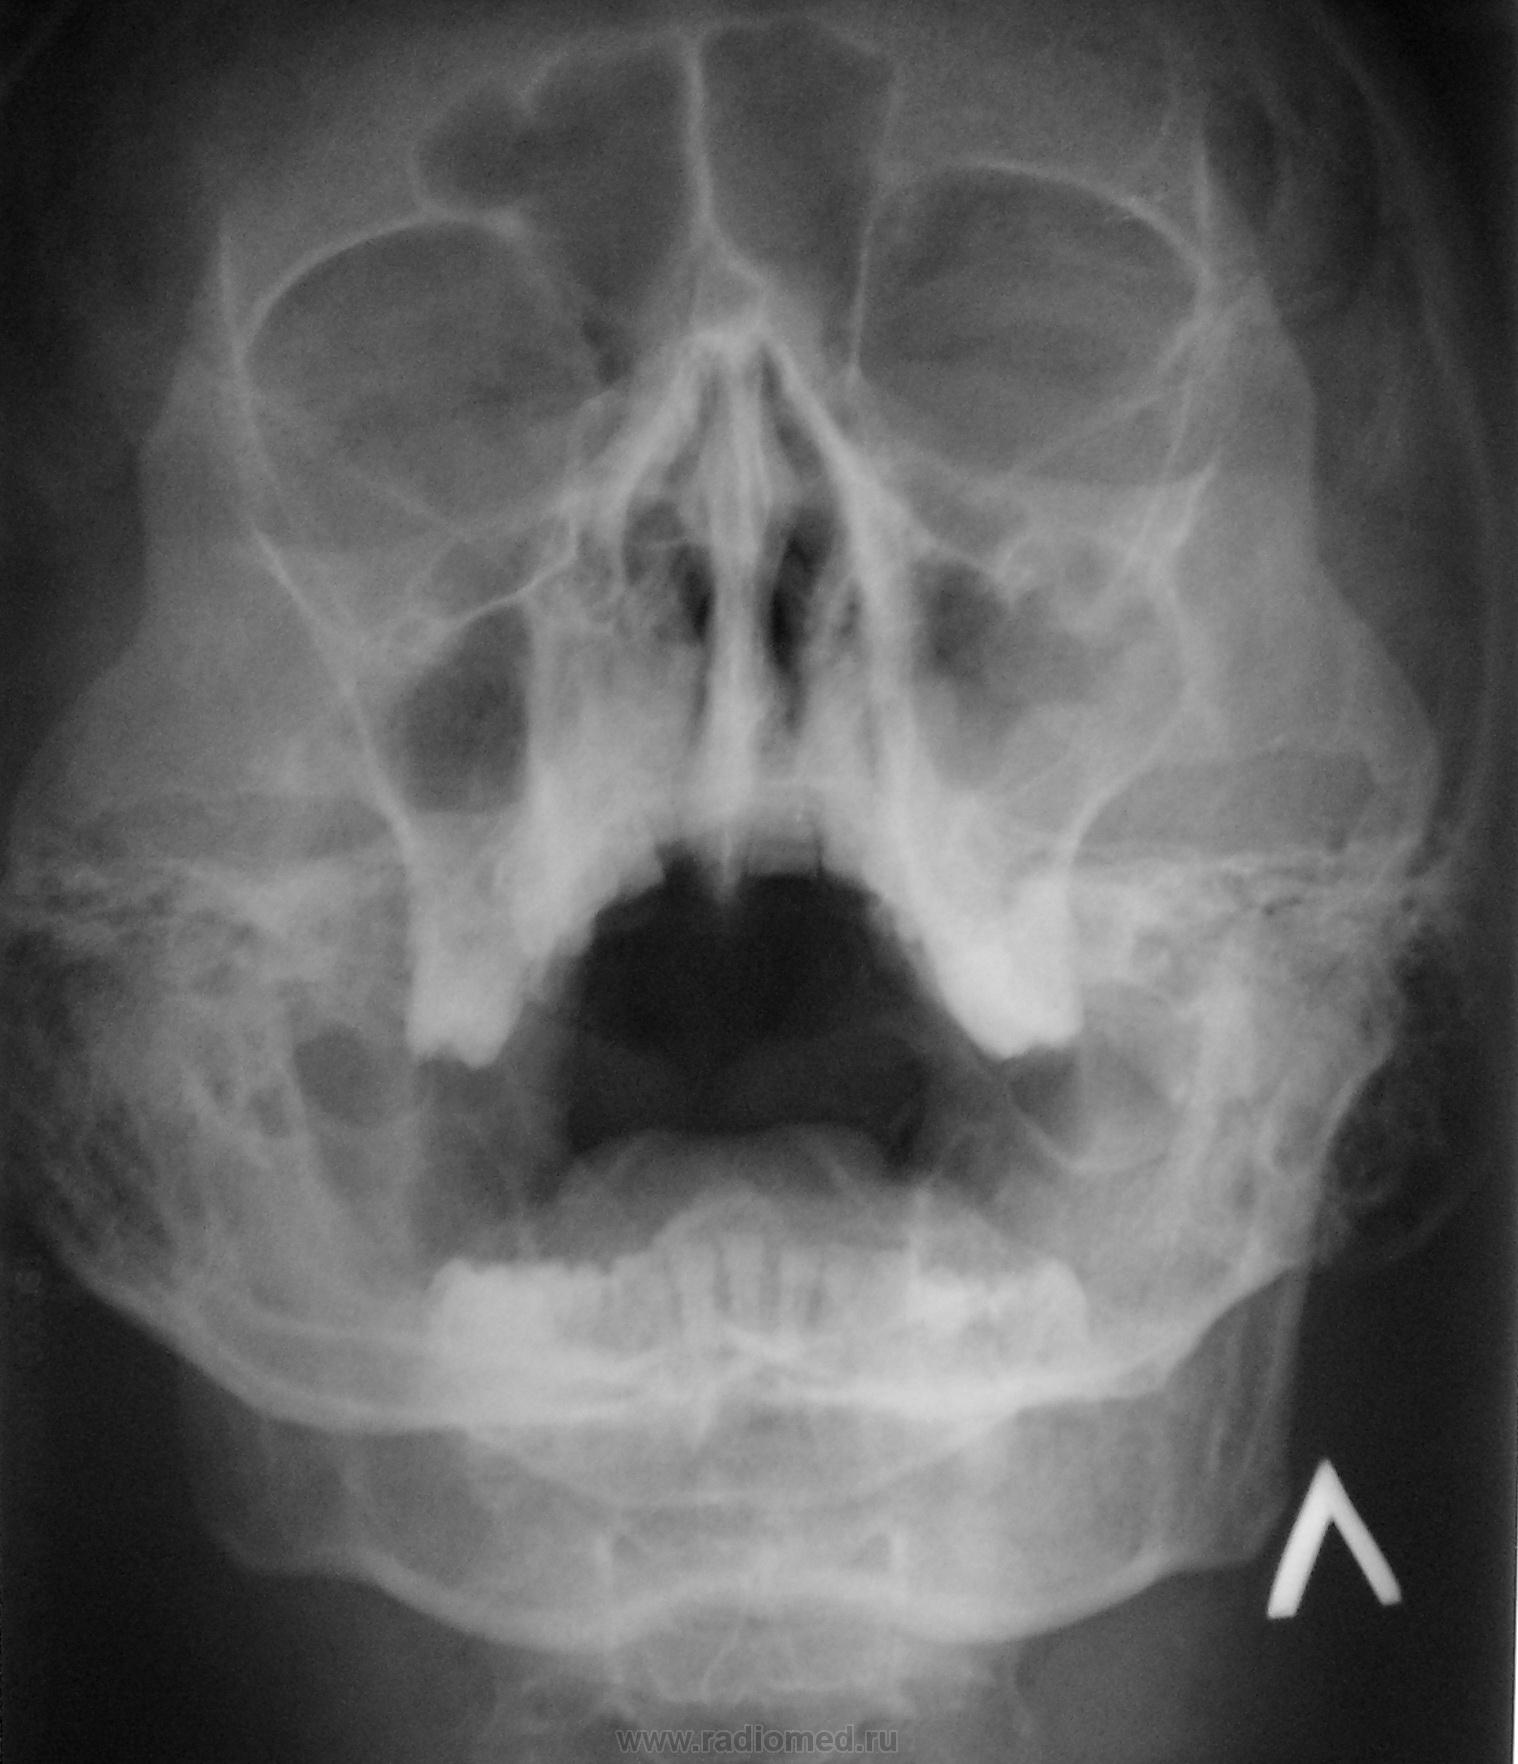

Мужчина средних лет был направлен ЛОР-ом для исключения патологии.

двусторонний гайморит, фронтит

Справа в гайморовой, то понятно - горизорнтальный уровень жидкости.

Ну, а слева, на мой взгляд, в гайморовой пазухе, похоже кистовидные образования, возможно одонтогенные.

Согласен с Валентином Львовичем, кроме слова "одонтогенных".

Позвольте с Вами, Валентин Львович, не согласиться - уровня в правой гайморовой нет, суммация теней...в т.ч. верхний край височной...а вот слева - согласен за "кистовидный" характер изменений.

Может быть и суммация, возможно..., но проверить, или отвергнуть легко - снимок в положении лежа, или лёжа на боку.